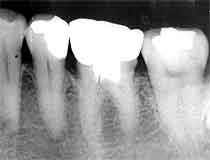

初診時 パノラマ 1年後 Dental写真

|5に隣接面カリエス

初診時口腔内およびX線所見:

口腔内清掃状態は比較的良好で、半埋伏状態の智歯周囲に歯肉の炎症が認められた。 口腔内の随所にC1〜C3程度のカリエスが認められた。

処置および経過:

主訴の智歯を上下・左右計4本抜歯するからわら、散在するカリエスの治療をおこなった。 |5のカリエス治療を行う寸前に来院が途絶えて1年経過。 |5の疼痛を訴えて来院されたが“時すでに遅し”で抜髄。

考察:

カリエスの進行は若年者ほど早いように思われるが、実際のデータとなると規格の統一が 難しく統計的手法で実証することはとても困難な作業です。 臨床症例の積み重ねすら難しい状況ですが、今後注意して探してみたいと思います。 ムシ歯があるにも関わらず意識して放置するわけにもいかず、患者さんの無断キャンセルと 再来をひたすら待つ因果なデータ収集です。

1年前に治療しておけば、抜髄の時期を10年は遅らすことができたのに!!?